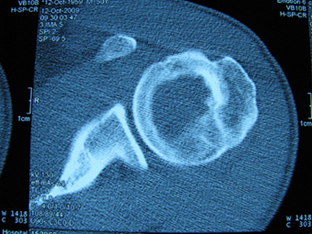

标题: X6404B:肱骨骨质破坏(CT片) [打印本页]

标题: X6404B:肱骨骨质破坏(CT片)

男,50岁,左肩部轻微疼痛,活动不便5个月就诊,近十天加重,无红肿热,间断理疗治疗无好转,既往5个月前左肩轻微拉伤史

骨巨?动脉瘤样骨囊肿?

内生软骨瘤。

内生软骨瘤。

内生软骨瘤?-----------

年纪大了,先要排除转移瘤。

髓腔内软组织肿块并斑片状钙化,考虑高分化软骨肉瘤可能性大。

考虑骨巨或动脉瘤样骨囊肿。

内生软骨瘤可能性大,期待结果。

孤立性骨囊肿。

内生软骨瘤可能性大

其内可见钙化,考虑软骨源性肿瘤,内生软骨瘤可能

但由于年龄较大,恶性软骨肉瘤待排

肱骨头内巨大软组织肿块并斑片状钙化,内生软骨瘤?骨巨细胞瘤?软骨粘液样纤维瘤?期待结果!

髓腔内软组织肿块并斑片状钙化,考虑高分化软骨肉瘤可能性大。

内生软骨瘤可能性大

肱骨头内巨大软组织肿块并斑片状钙化,内生软骨瘤?骨巨细胞瘤?软骨粘液样纤维瘤?期待结果

考虑内生软骨瘤?骨巨细胞瘤?

内生软骨瘤?骨巨细胞瘤?

先要排除转移瘤。